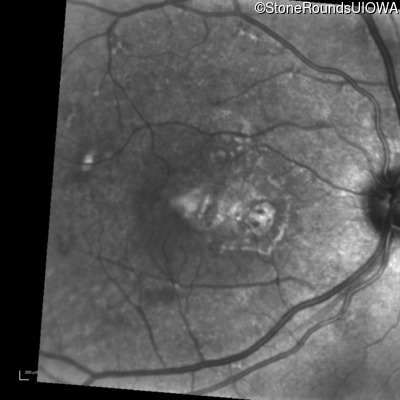

Fluorescein Angiography - Left - 20/20